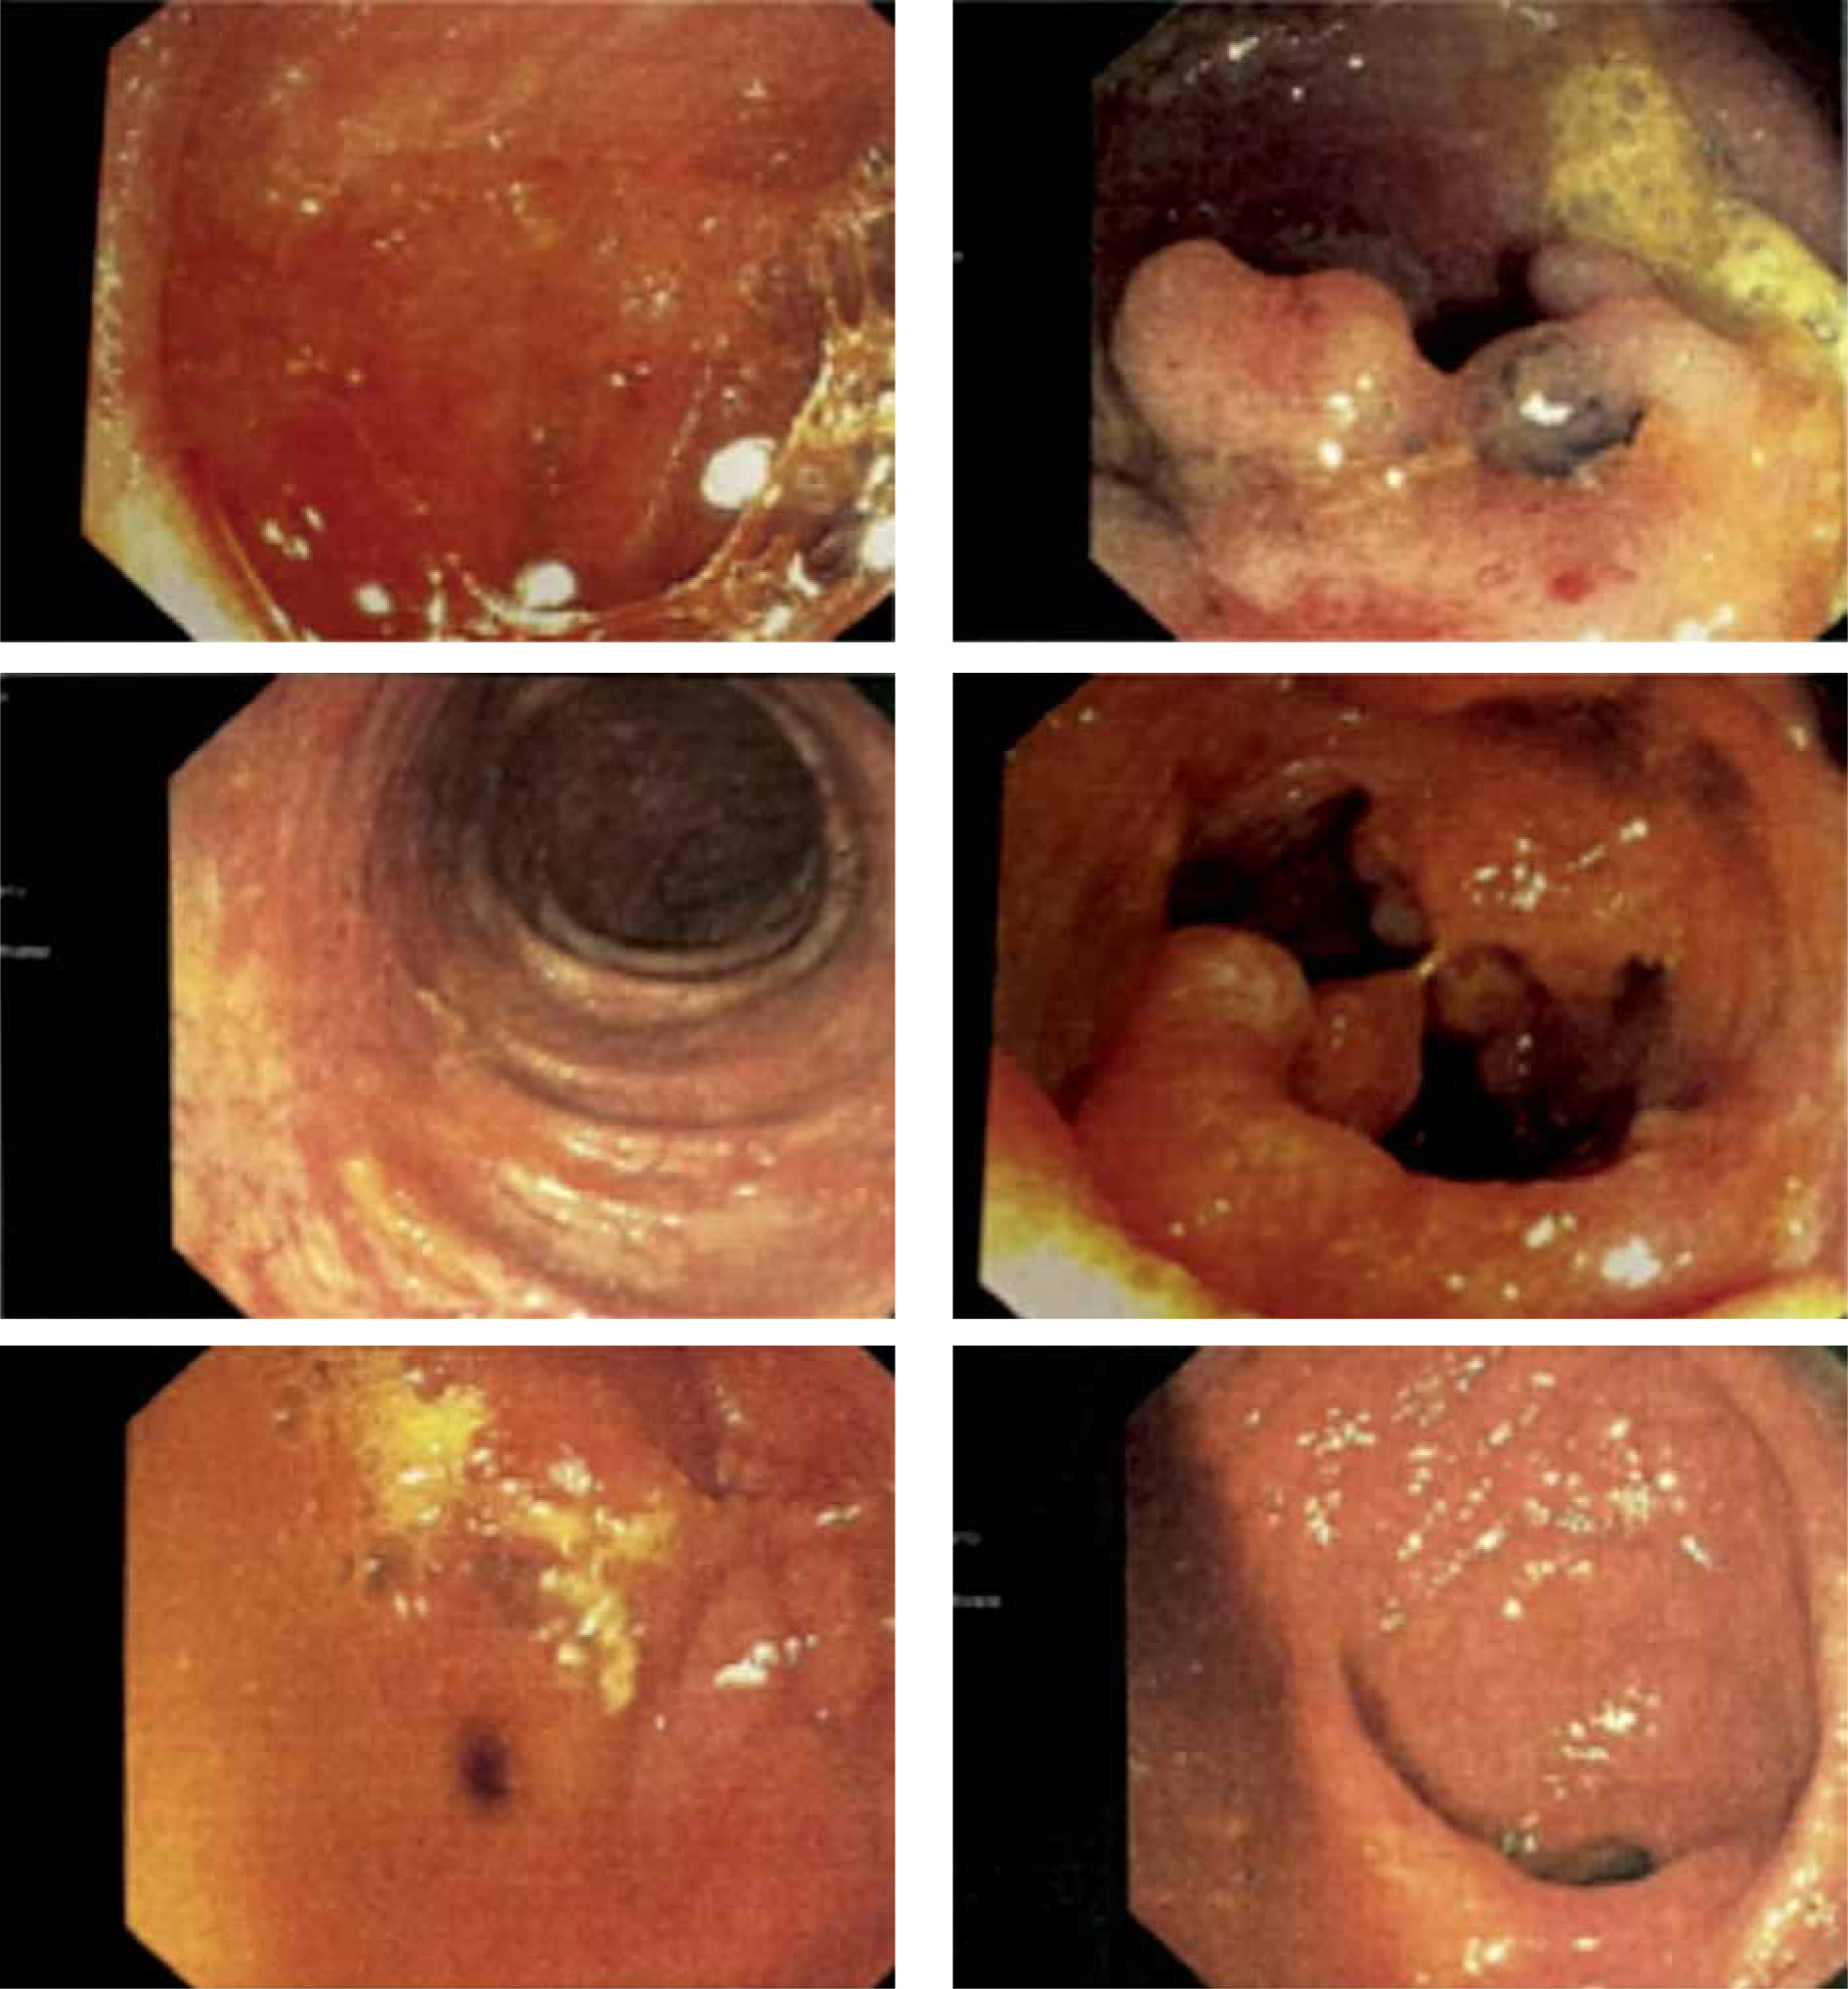

On 16 March 2021 CDI was confirmed with the Toxin A/B test. On 25 March 2021 the patient was admitted to the Gastroenterology Department in Konin. She was treated with vancomycin for 14 days (2 g/day) for CDI and mesalazine and hydrocortisone for UC. Nevertheless, the diarrhoea persisted. After consultation, the patient was discharged on 9 April and redirected to the Department of Digestive Tract Diseases in Norbert Barlicki Memorial University Hospital in Lodz. On 12 April a colonoscopy was performed, which confirmed the previous diagnosis of CDI and UC. There was a polypoid lesion in the orifice of vermiform appendix. The mucosa was swollen, hyperaemic with blurred vascular pattern along the entire length of the intestine, with numerous pseudopolyps, mainly in the descending colon and sigmoid colon (Figure 1).

Figure 1

Swollen, hyperaemic mucosa with blurred vascular pattern along the entire length of the intestine, with numerous pseudopolyps, mainly in the descending colon and sigmoid colon